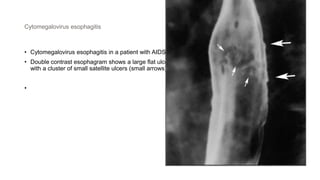

Cytomegalovirus esophagitis

• Cytomegalovirus esophagitis in a patient with AIDS

• Double contrast esophagram shows a large flat ulcer in profile (large arrows) in the midesophagus

with a cluster of small satellite ulcers (small arrows)